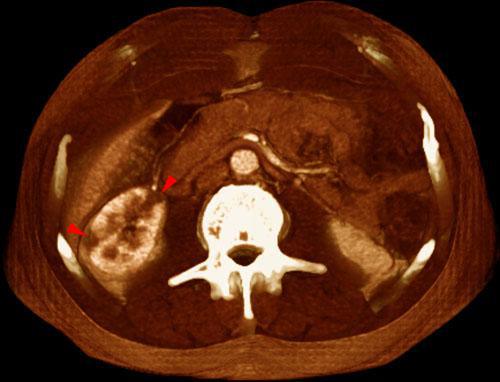

Infartos renales múltiples

VR seccional. Visión axial caudal. TC contrastado en fase venosa. Lesiones hipodensas multifocales y periféricas (puntas de flecha) en un paciente con neoplasia broncopulmonar